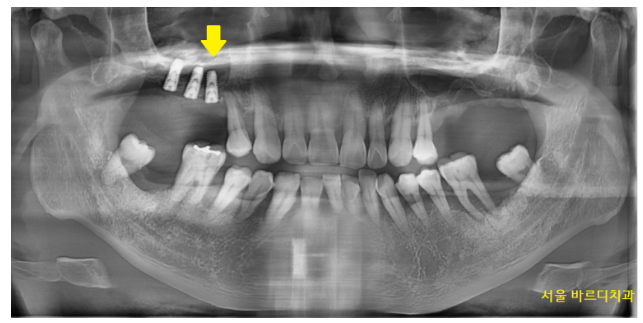

230327

그래서 그런가 입안 상태도 좋지 못했습니다.

정상적인 치아가 없을정도였죠.

안 흔들리는 치아가 없었습니다.

뽑힌 치아도 많았고

앞으로 뽑을 치아도 상당했습니다.

윗니는 개수로만 4개 없음

아랫니는 2개 없음

앞으로 뽑아야하는 치아들